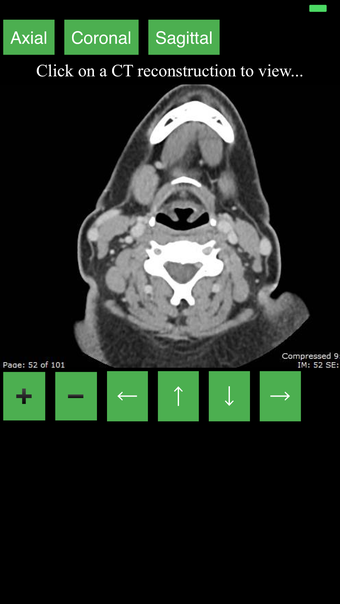

Ta aplikacja jest najwygodniejszym sposobem na przeglądanie i badanie przekrojowo anatomii człowieka na skanie CT. Może być używana jako materiał referencyjny i narzędzie edukacyjne.

Aplikacja wyświetla przekrojowy obraz tomograficzny ciała człowieka i używa systemu kodowania kolorów, aby łatwo identyfikować różne struktury tkanek miękkich i kości. Może również być używana do badania określonej części ciała, takiej jak szyja, czaszka, obręcz barkowa lub klatka piersiowa.

Użytkownik może przesuwać obraz i powiększać go, aby lepiej zidentyfikować struktury i powiększyć obraz do dalszych badań.